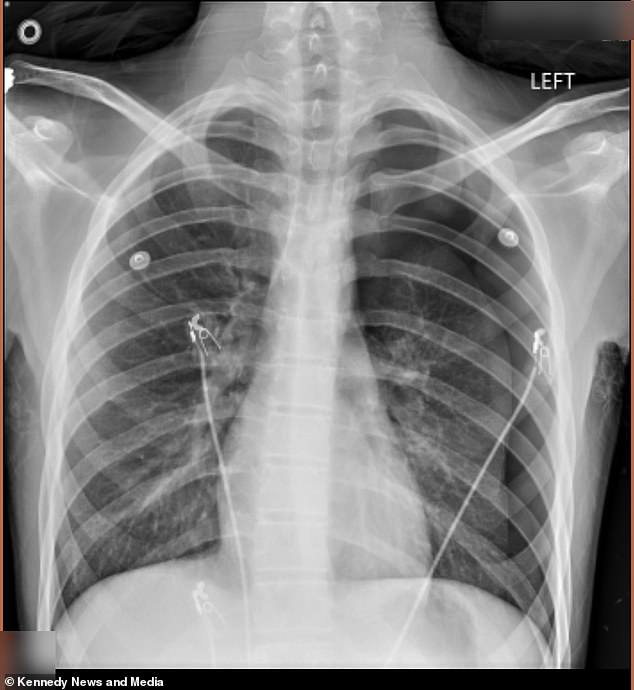

A Kentucky mother is issuing a stark warning after her teenage son's life was turned upside down by a dangerous habit he adopted to fit in with his peers. Cameron Vann, known as Dodge, began vaping two years ago to appear 'cool' in front of his friends, but he kept the secret from his mother, Crystal Vann, until it was too late. In September 2025, Dodge emerged from the school bus pale and in severe pain, prompting Vann to rush him to the emergency room. A chest x-ray revealed that 50 percent of his left lung had collapsed, a condition known as a pneumothorax, which occurs when air enters the chest cavity and exerts pressure on the lung.

The severity of the situation forced doctors to perform a surgical intervention, inserting an 18-inch tube into Dodge's chest to remove the excess air and allow his lung to re-expand. However, the teenager continued to vape in secret, unaware of the long-term consequences of his actions. It wasn't until January 2026 that Dodge once again called his mother, out of breath and in intense pain, signaling the recurrence of the condition. This time, the situation was even more dire. Doctors warned that if they hadn't acted quickly, Dodge could have died in the hospital lobby.

The second collapse required an even more aggressive surgical procedure known as a pleurodesis. During this operation, doctors scraped the lining of Dodge's lung and stapled fluid or air-filled blisters called blebs to the top of his lung, effectively reattaching it to the chest wall. The experience left Vann in a state of shock and fear. 'He went through a lot. It was horrible,' she said. 'I thought, "Why him?" I feared he was going to die.' Vann expressed frustration over the fact that Dodge's friends had first introduced him to vaping, and she now strongly advises others to avoid the practice.